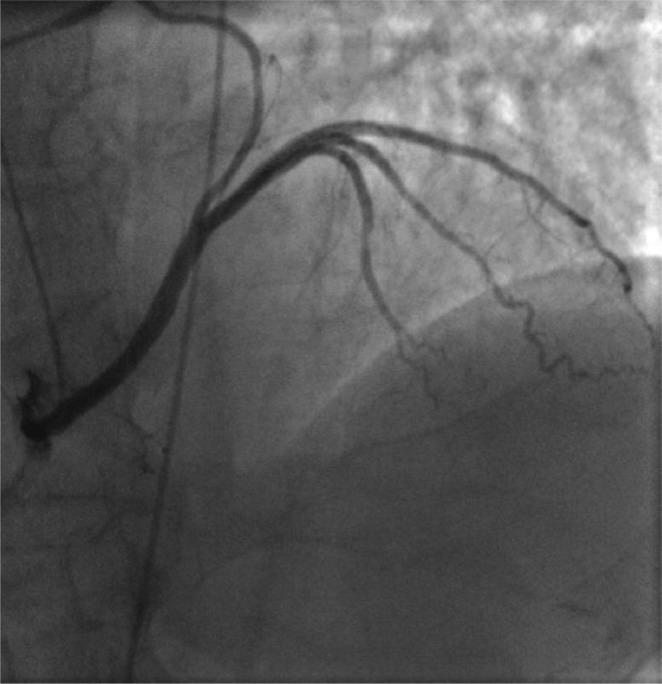

Coronary artery anomalies (CAAs) may be discovered more often as incidental findings during the normal diagnostic process for other cardiac diseases or less frequently on the basis of manifestations of myocardial ischemia. The cardiovascular professional may be involved in their angiographic diagnosis, functional assessment and eventual endovascular treatment. A complete angiographic definition is mandatory in order to understand the functional effects and plan any intervention in CAAs: computed tomography and magnetic resonance imaging are useful non-invasive tools to detect three-dimensional morphology of the anomalies and its relationships with contiguous cardiac structures, whereas coronary arteriography remains the gold standard for a definitive anatomic picture. A practical idea of the possible functional significance is mandatory for deciding how to manage CAAs: non-invasive stress tests and in particular the invasive pharmacological stress tests with or without intravascular ultrasound monitoring can assess correctly the functional significance of the most CAAs. Finally, the knowledge of the particular endovascular techniques and material is of paramount importance for achieving technical and clinical success. CAAs represent a complex issue, which rarely involve the cardiovascular professional at different levels. A timely practical knowledge of the main issues regarding CAAs is important in the management of such entities.

冠状动脉异常(CAAs)可能在其他心脏疾病的常规诊断过程中作为偶然发现而被更频繁地发现,或者更不频繁地基于心肌缺血的表现。心血管专业人员可能参与其血管造影诊断、功能评估和最终的血管内治疗。为了了解功能影响并计划对 CAA 进行任何干预,需要进行完整的血管造影定义:计算机断层扫描和磁共振成像是检测异常的三维形态及其与相邻心脏结构关系的有用非侵入性工具,而冠状动脉造影仍然是明确解剖图像的金标准。为了决定如何处理 CAA,需要对可能的功能意义有一个实际的了解:非侵入性应激试验,特别是有或没有血管内超声监测的侵入性药物应激试验,可以正确评估大多数 CAA 的功能意义。最后,了解特定的血管内技术和材料对于实现技术和临床成功至关重要。CAA 是一个复杂的问题,很少涉及不同层次的心血管专业人员。及时了解有关 CAA 的主要问题对于此类实体的管理非常重要。